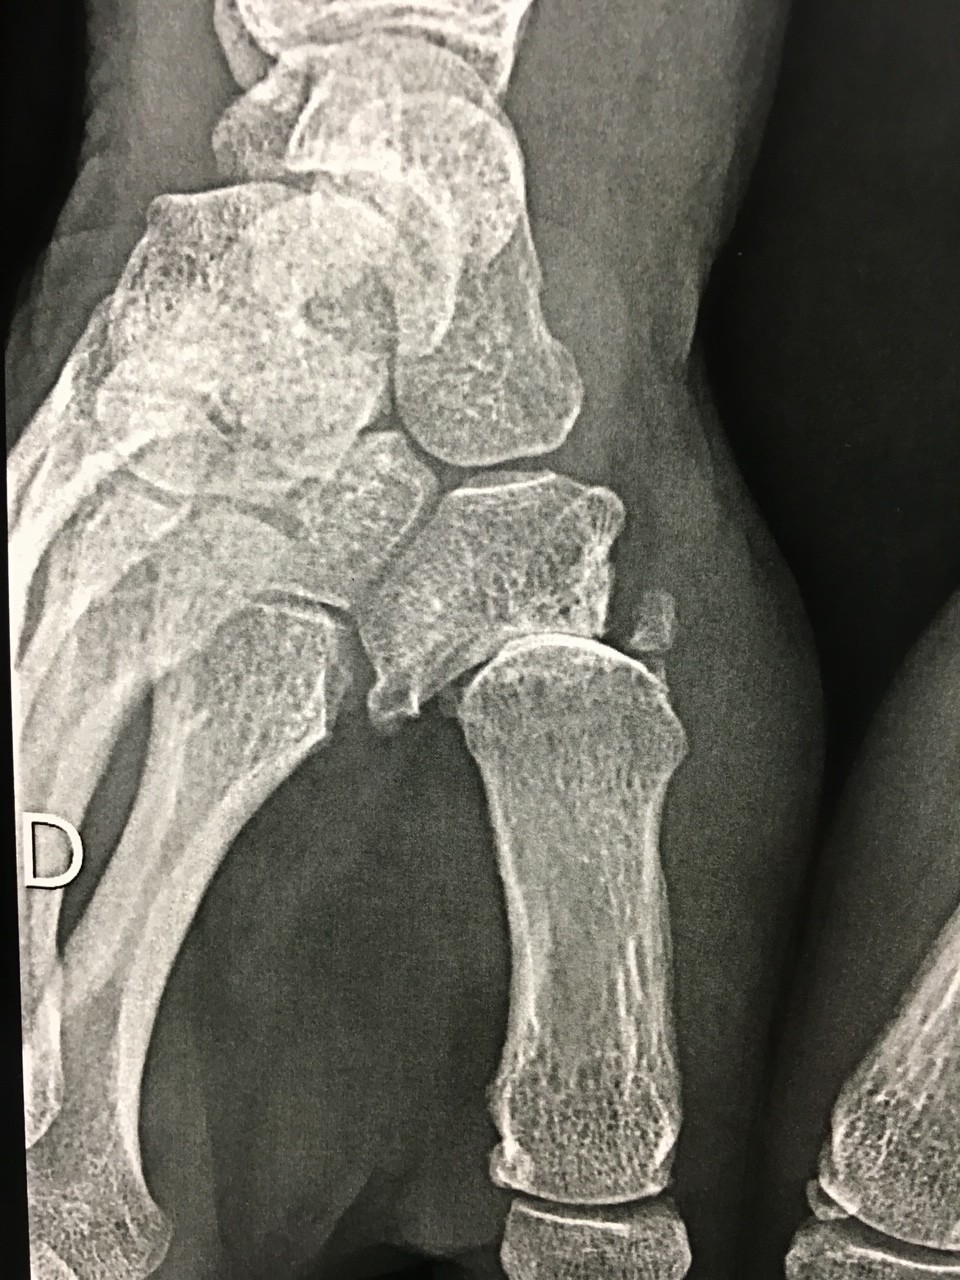

C’est une usure du cartilage d’une des articulations les plus importantes du pouce. Cette articulation sert à opposer le pouce aux autres doigts pour permettre la fonction de pince. Elle s’use au cours du temps, touche le plus souvent les femmes autour de 50 ans. Le plus souvent, il n’y a pas de cause évidente et il peut y avoir un caractère familial. Les hommes peuvent être aussi atteints et on retrouve alors souvent une cause traumatique .

Cette destruction du cartilage trapezométacarpien occasionne une perte de force, des douleurs et également une déformation du pouce. J’entends souvent, que s’agissant d’arthrose , rien n’est possible. C’est inexact, des traitements efficaces existent pour cette arthrose particulièrement.

Le diagnostic se fait dès l’examen clinique. Les radiographies de l’articulation trapèzo-metacarpienne selon les incidences de Kapandji peuvent suffire dans la majorité des cas. Dans certains cas complexes, un scanner sera prescrit par le chirurgien. Un syndrome du canal carpien touche pratiquement un tiers des femmes concernées par l’arthrose de la base du pouce. Il est alors possible d’envisager le traitement des deux problèmes en même temps. Il est donc justifié de réaliser un électromyogramme dans le cadre du bilan avant traitement.

Le traitement est médical dans un premier temps. Des anti-inflammatoires sont prescrits en cas de poussée pour une courte durée. Je recommande également et en même temps le port d’une petite orthèse que l’on trouve en pharmacie. Celle-ci peut être portée la nuit pour mettre le pouce au repos. C’est relativement efficace au début. Des infiltrations peuvent s’avérer utiles mais elles ne permettent pas de stopper l’évolution, ni traiter la cause. Si le traitement médical ne permet plus un soulagement durable, la chirurgie doit être envisagée et il n’est pas toujours très prudent d’attendre que les déformations soient graves. Moins le pouce est déformé plus le résultat fonctionnel est bon. Il existe trois grandes façons de traiter l’arthrose de la base du pouce :